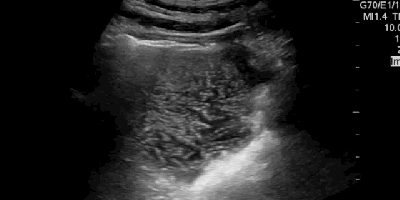

Make the POCUS diagnosis, sono of the week, Sono Stuff